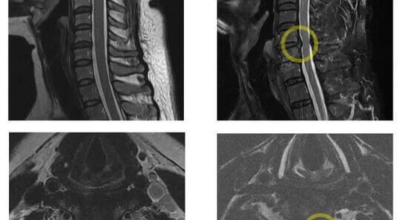

경추 사이의 추간판(디스크)이 탈출 또는 파열되어 경추신경이 자극이나 압박을 받아 통증이 생기는 증상을 말해요. 경추는 운동성이 큰 부위로 추간판이 압력을 받으면 튀어나와 척수나 신경을 압박하게 되는데요 목디스크는 퇴행성 변화 이후에 발생되기 때문에 많은 환자들이 만성적인 통증을 지니고 있는 경우가 많아요. 급성으로 생기는 경우는 교통사고, 추락, 스포츠 활동에 의한 목 부상으로 나타나기도 해요. 20대부터 가벼운 초기 증상으로 시작하여 옳지 않은 습관으로 악화되거나 호전되기를 반복해요. 나이가 들면 퇴행성 변화로 40~50대에 가장 많은 환자 수를 보인다고 합니다

비수술적 치료가 효과가 없다거나 디스크의 신경압박이 정도가 심한 경우엔 시술할 관조차 들어갈 공간이 없으니 비수술을 고집하는 경우 주변의 정상조직까지 훼손이 될 위험이 있답니다. 미세 현미경 수술이나 인공 디스크 치환술 및 경추유합술을 통해서 치료가 가능한데 가급적 비수술치료가 권장되지만 정확한 진단이 먼저되어야 하기 때문에 자세한 사항은 전문의와 상담해서 결정하는 것이 좋을겁니다.